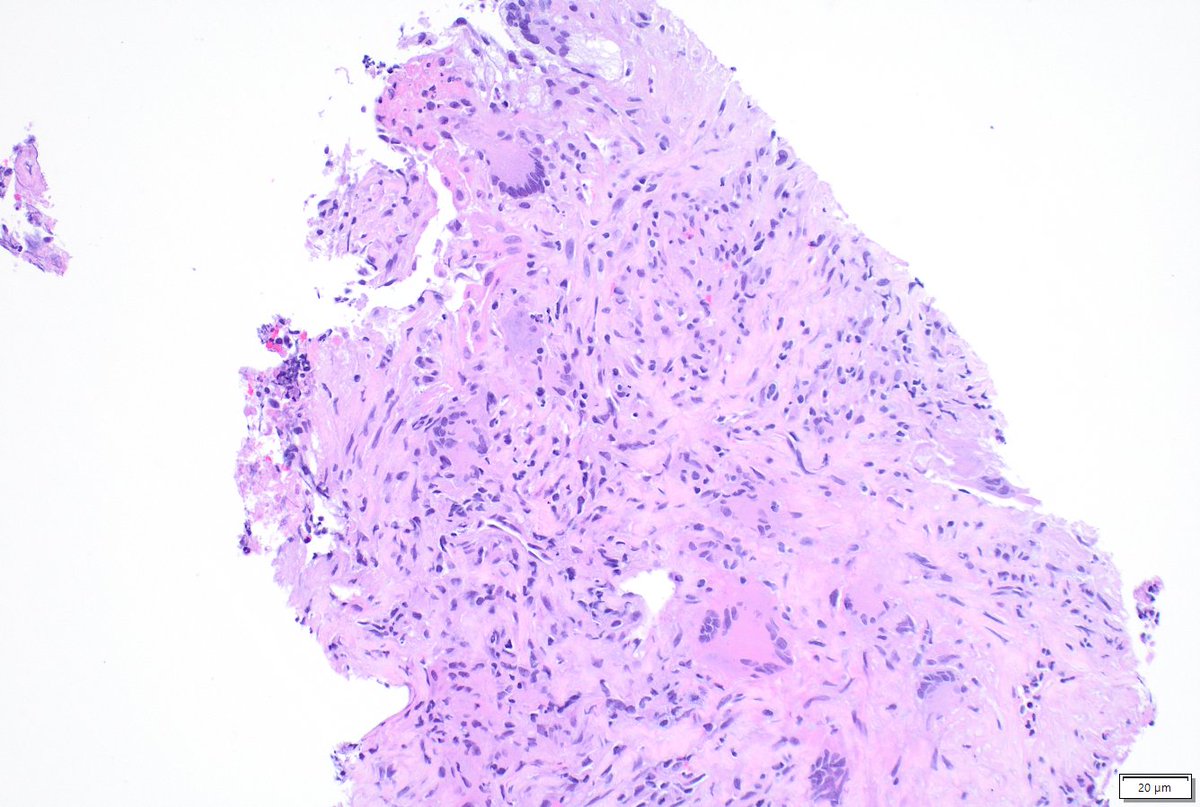

What to do with ill-formed interstitial granulomas on lung resections for malignancy? When are interstitial mononuclear inflammatory cells too numerous? (Same case, away from tumor) #moffitt #moffittpath #lungpath #moffittpathology